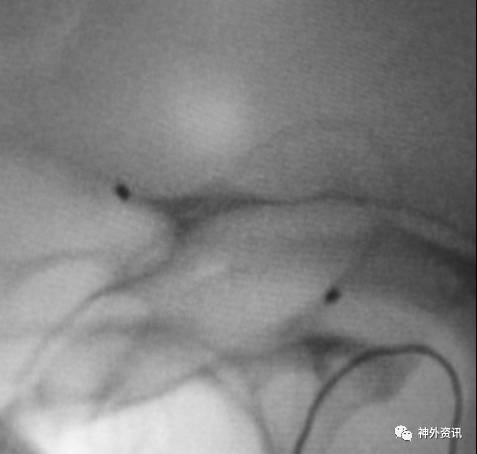

猪尾塑形

猪尾左行和右行

微导管尾端向下直立,头端向前弯曲时,头端相对左偏为左行,右偏为右行。

指向下方的颈内动脉眼段或床突段动脉瘤(颈动脉窝动脉瘤)

指向下方的颈内动脉后交通段或脉络膜段动脉瘤

(1)左侧颈内动脉-猪尾左行

(2)右侧颈内动脉-猪尾右行

病例一

病例二

病例三

病例四

单弯导管在血管内呈螺旋状前进,因此微导管的塑形需要考虑到其在血管内螺旋前进的因素